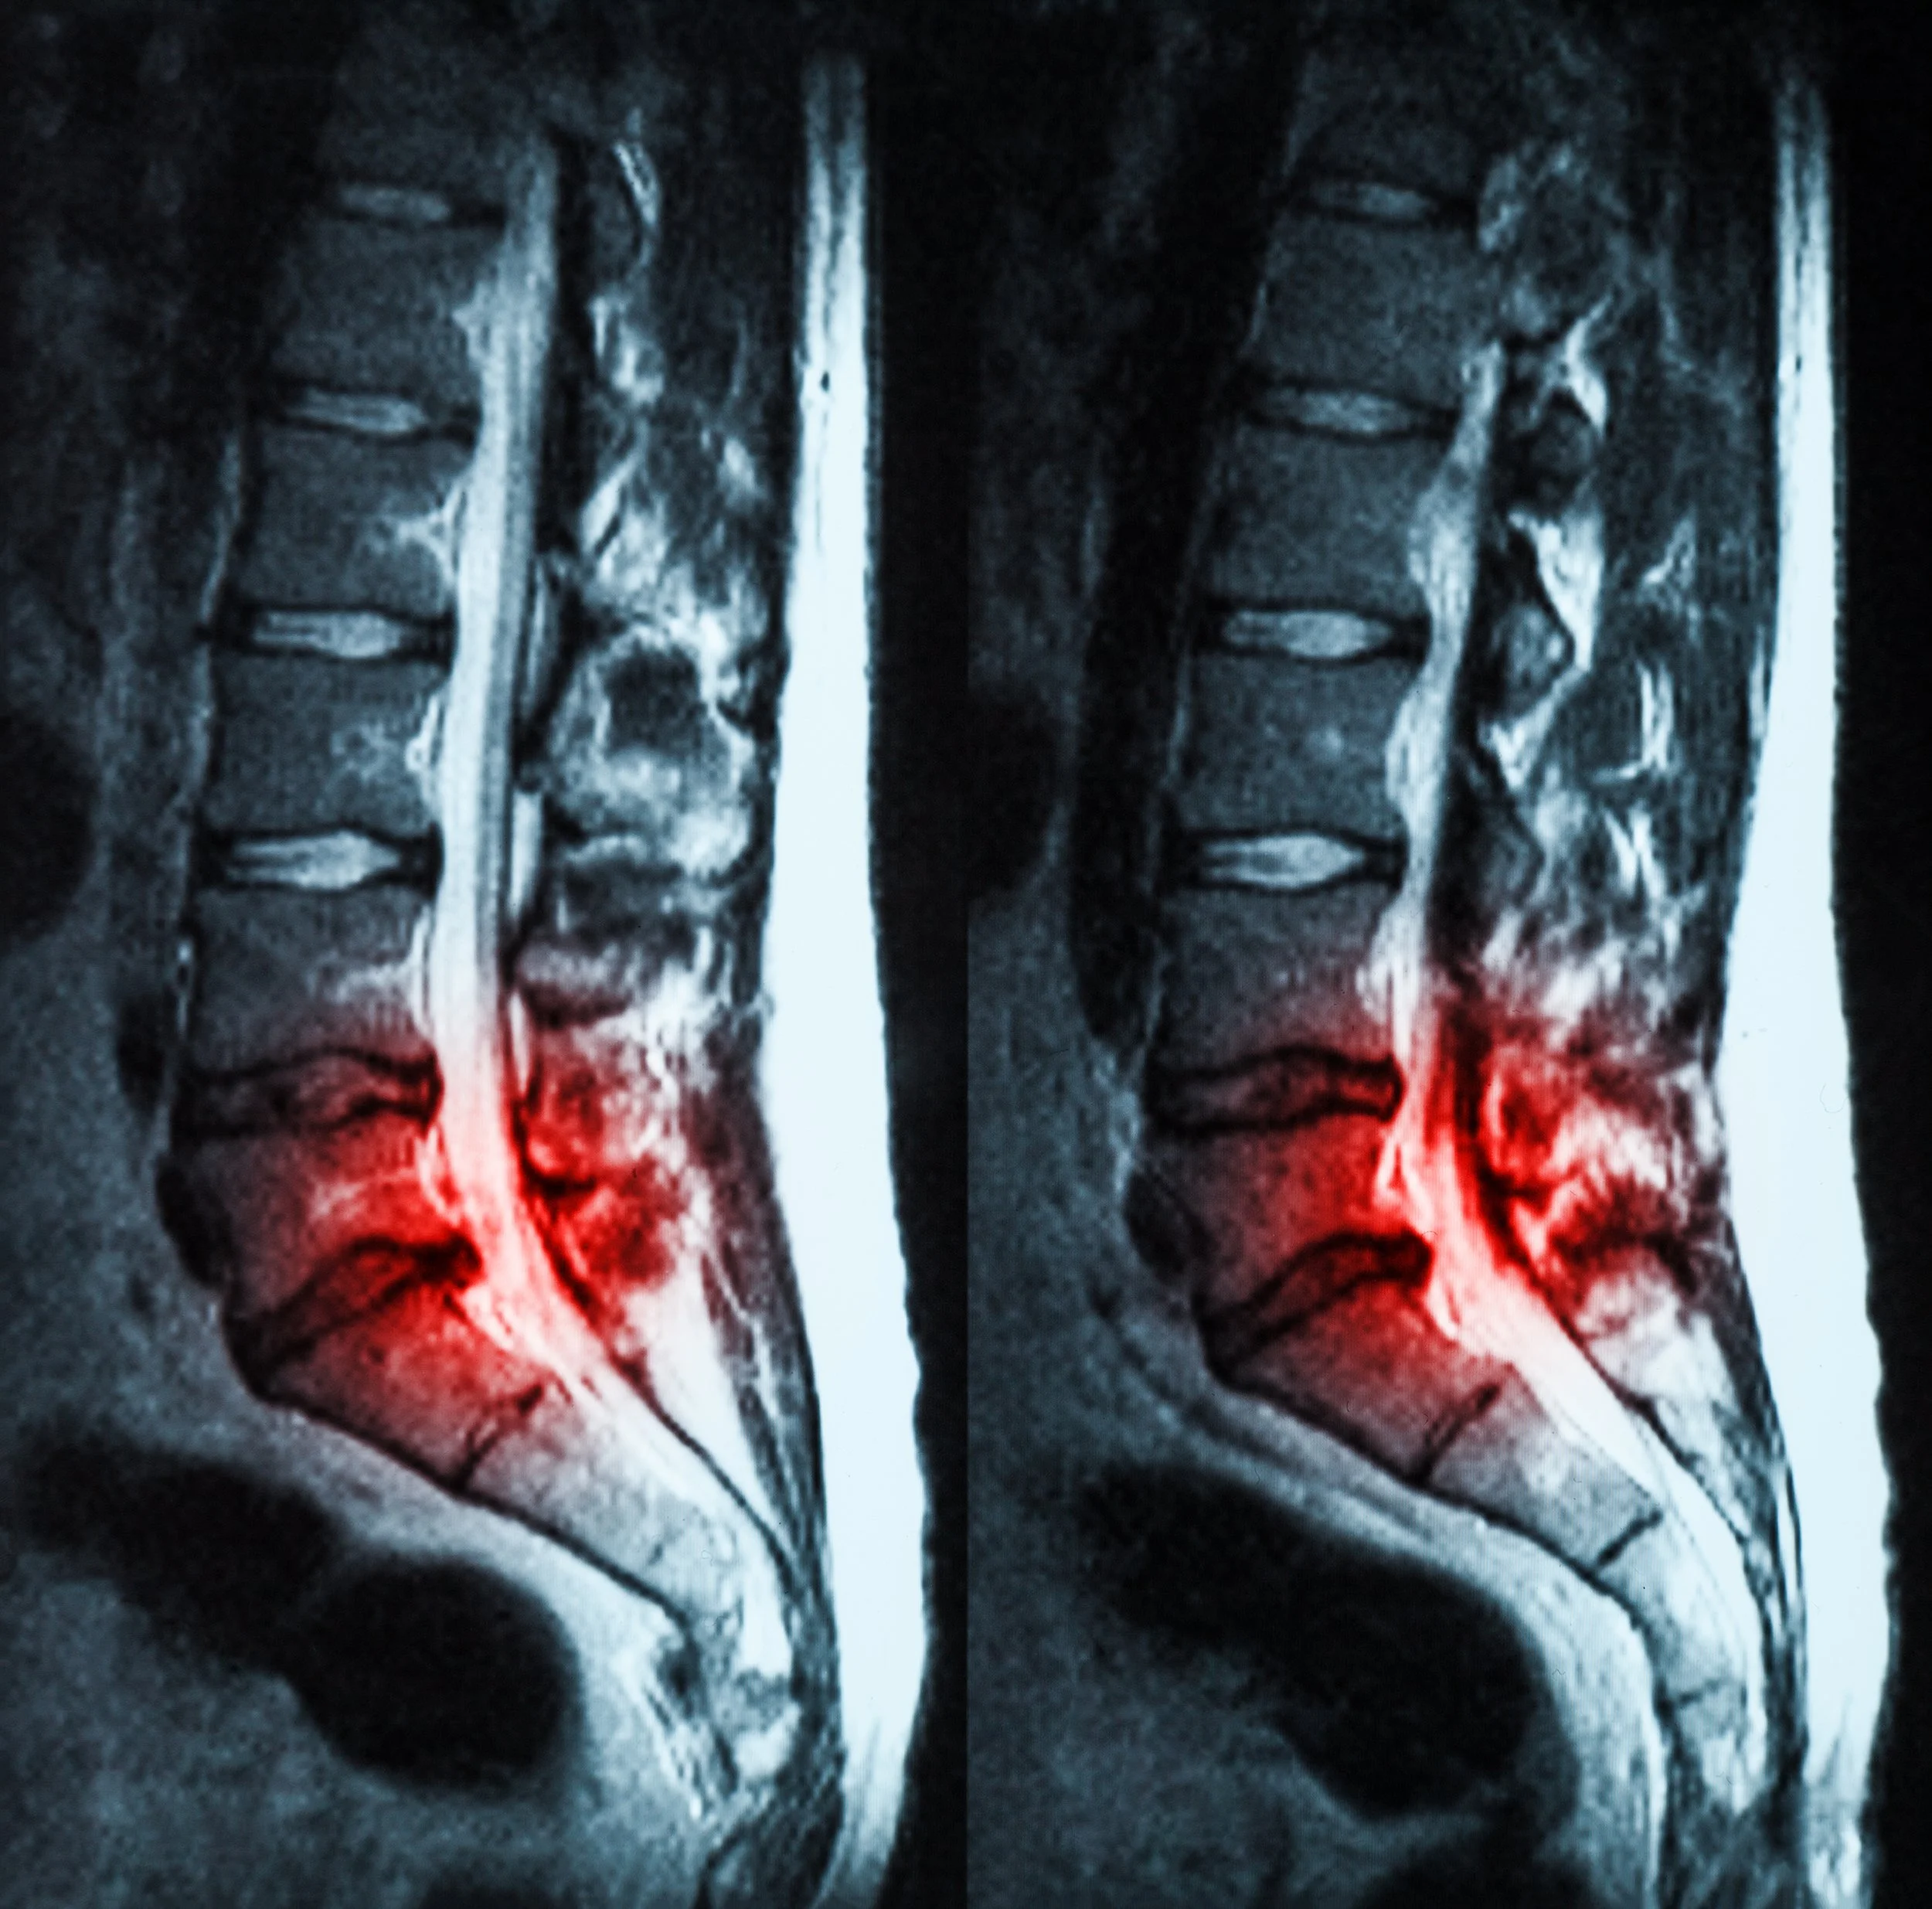

Ved behov kan man henvise til MR-undersøkelse, som kan vise om det foreligger prolaps og om en nerve er påvirket. I Norge anbefaler nasjonale retningslinjer ofte konservativ behandling først, da mange prolaps bedres over tid.

Når trenger man MR ved prolaps?

MR brukes vanligvis dersom symptomene er sterke, varer over tid, eller dersom det er tegn til betydelig nervepåvirkning. I henhold til nasjonale retningslinjer i Norge anbefales det ofte å avvente MR de første ukene, da mange ryggplager og prolaps kan bedres med konservativ behandling. MR vurderes vanligvis dersom symptomene ikke bedres etter 4–6 uker, eller hvis det er mistanke om mer alvorlig tilstand.